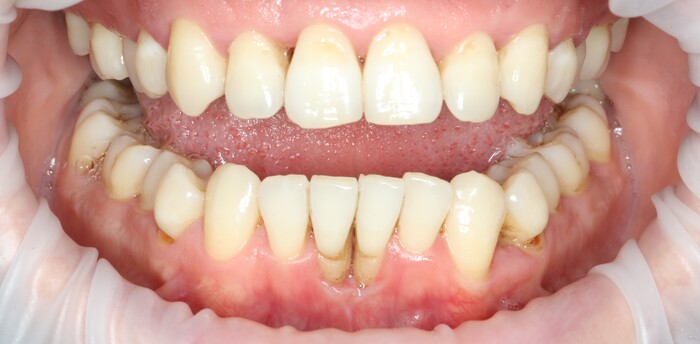

С другой стороны… с этого мы начали:

а на этом остановились: